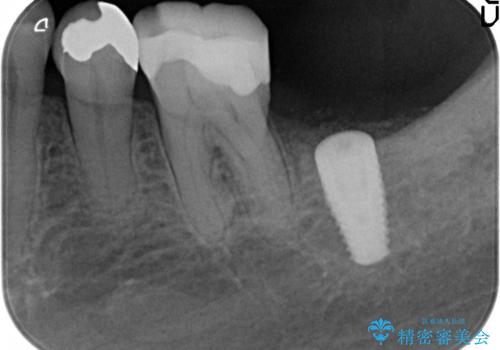

- 69.4万円 内訳:左下7(ストローマンインプラント24.2万円 インプラント用仮歯2.2万円 骨増成5.5万円 カスタムアバットメント11万円 FGG(遊離歯肉移植術)11万円 静脈内鎮静5.5万円)費用は治療当時の料金となります

歯肉移植を行うと、炎症に強く歯周病になりにくい歯周組織の状態でのインプラント補綴が可能になります。

他の歯の治療もあり治療に時間をかけることが問題なかった点、また、審美領域ではない点、患者様が時間をかけてもいいのでお手入れしやすく長持ちするインプラントを希望していたことから2回法を選択しております。一回法のメリットは今回は特にありませんでした。患者様のご希望もふまえ、無理せず抜歯後しっかり骨ができるのを待って、角化歯肉を増やすため歯肉移植も行いました。